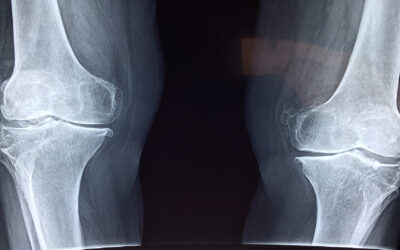

ทราบหรือไม่ว่า 2 ใน 3 ของคนอ้วน จะมีภาวะข้อเข่าเสื่อม ร่างกายของมนุษย์เรามีการสร้างกระดูก และการทำลายกระดูกไปพร้อม ๆ กัน